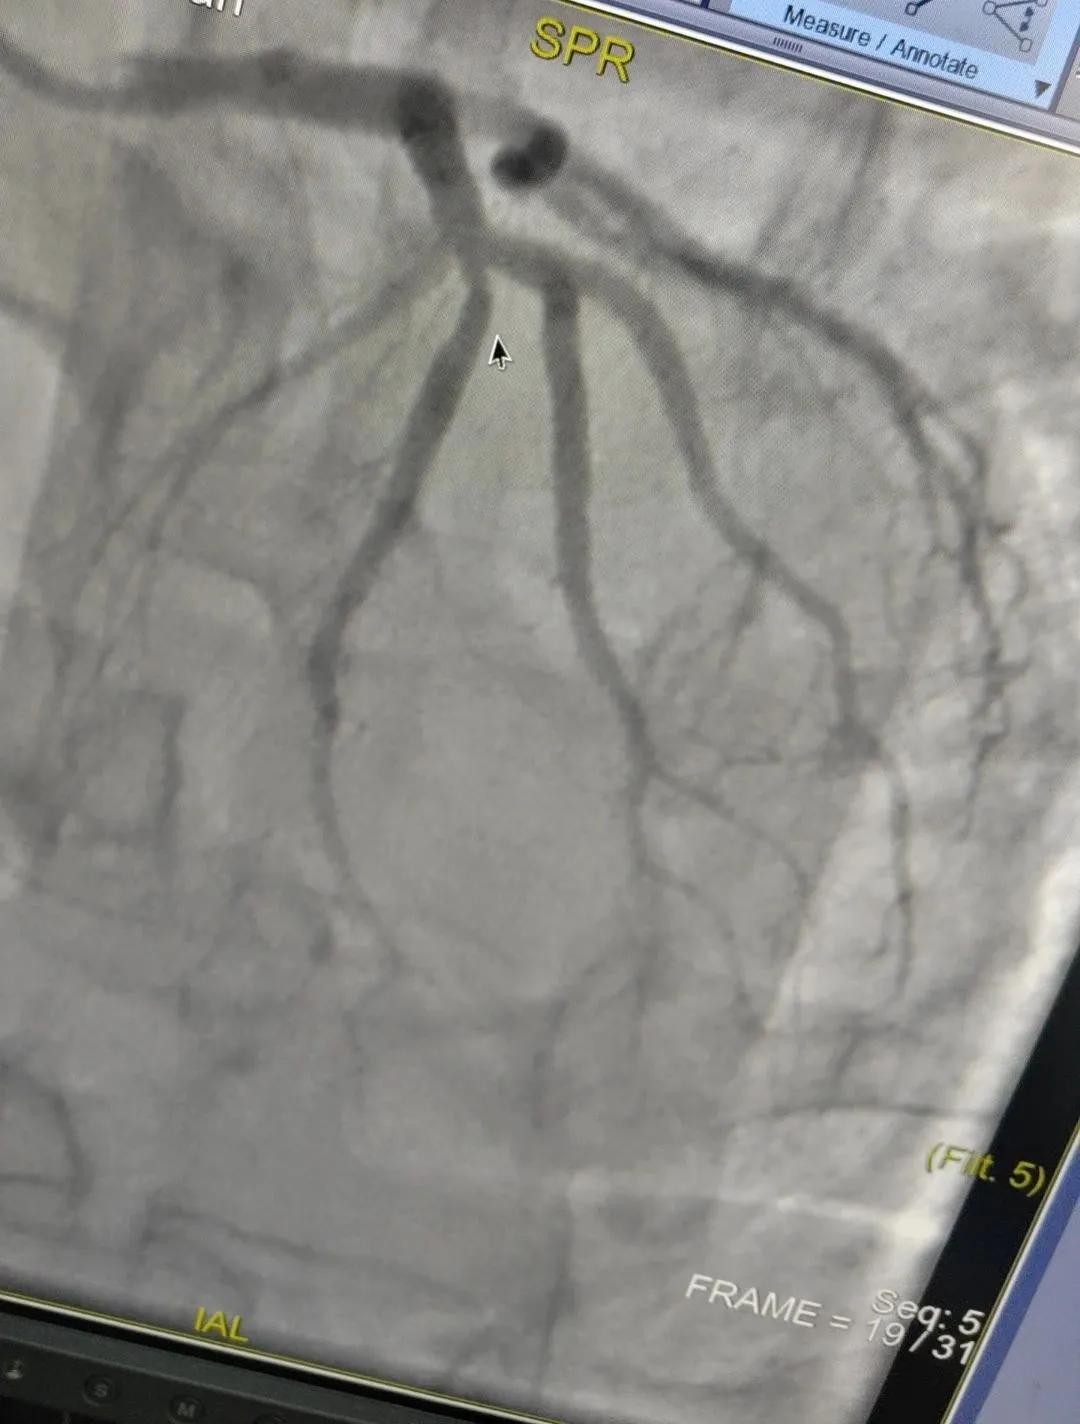

患者男,37歲,兩周前無明顯誘因突發(fā)頭昏,伴右側(cè)肢體無力來院就診,經(jīng)過對(duì)患者病情的評(píng)估以及心內(nèi)科和腦病科醫(yī)生聯(lián)合會(huì)診,需對(duì)患者進(jìn)行心腦血管聯(lián)合造影手術(shù)。由神經(jīng)內(nèi)科楊慶堂副主任與心血管內(nèi)科陳云副主任帶領(lǐng)各自的介入團(tuán)隊(duì)為該患者順利進(jìn)行了全腦血管造影術(shù)+心血管造影的介入檢查。

術(shù)中心血管造影顯示:LAD中段發(fā)出D1處可見約50%節(jié)段性狹窄,RCA中段狹窄約40%,PLA可見約70%狹窄病變。

腦血管造影顯示:左側(cè)頸內(nèi)動(dòng)脈嚴(yán)重遷曲,左側(cè)大腦前動(dòng)脈未顯影,左側(cè)大腦中動(dòng)脈M1中段以遠(yuǎn)未顯影,M1近段串珠樣嚴(yán)重狹窄,顱底可見少量煙霧血管,后交通動(dòng)脈未開放;右側(cè)頸內(nèi)動(dòng)脈嚴(yán)重遷曲。右側(cè)大腦前動(dòng)脈A1段嚴(yán)重遷曲。

心腦聯(lián)合造影不僅明確患者的病因和病變血管,還為下一步治療提供了有力的依據(jù)。